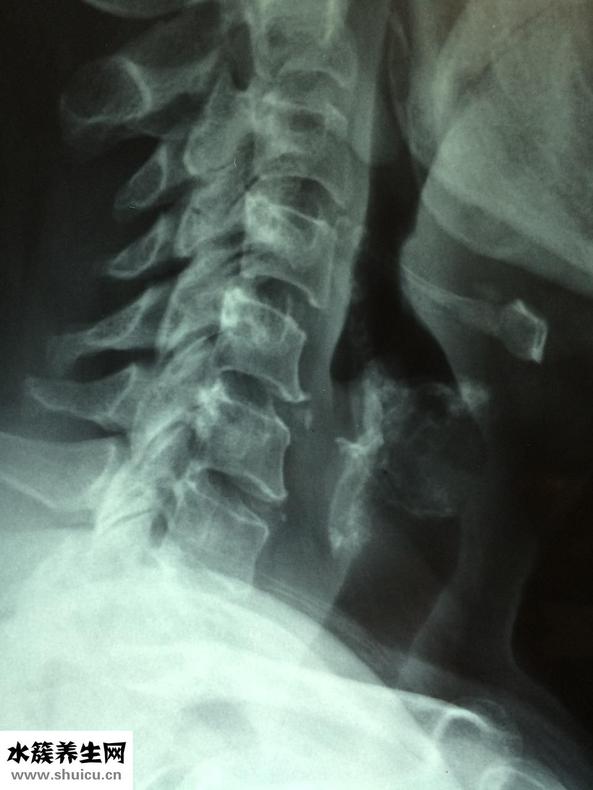

1、最先需要大伙儿了解一下,眩晕症的病症有很多,头昏便是在其中一种,而且很多人都有头晕眼花的病症,这主要是颈椎骨及其腰椎间盘退行性变造成的,也有便是椎动脉血管堵塞,脑部的血供不顺畅,眼底黄斑神经功能紊乱及其病菌感染等病症也会造成眩晕症。因此,对眩晕症要有一个简易的了解,而且要到医院门诊去做一些查验,看一下究竟是什么原因,随后才好目的性的医治。